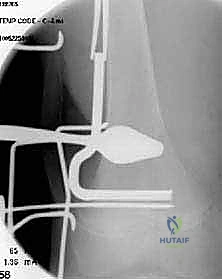

الخطوة الأولى: التحضير والتخدير

تتم العملية تحت التخدير العام أو النصفي بناءً على تقييم طبيب التخدير. يتم وضع المريض على طاولة العمليات الجراحية المجهزة بأجهزة الأشعة السينية المباشرة (C-arm) لضمان الدقة المطلقة أثناء كل خطوة. يتم استخدام عاصبة هوائية (Tourniquet) لتقليل النزيف الجراحي.

الخطوة الرابعة: التثبيت الداخلي القوي (Internal Fixation)

لضمان التئام العظم في وضعه الجديد المستقيم، يجب تثبيته بقوة شديدة. يستخدم الدكتور هطيف أحدث الشرائح المعدنية التشريحية ذاتية القفل (Locking Compression Plates) والمسامير المصنوعة من التيتانيوم النقي. يتم تثبيت الشريحة على جانب عظمة الفخذ، مما يوفر استقراراً ميكانيكياً هائلاً يسمح للمريض ببدء العلاج الطبيعي في وقت مبكر دون خوف من تحرك العظام.